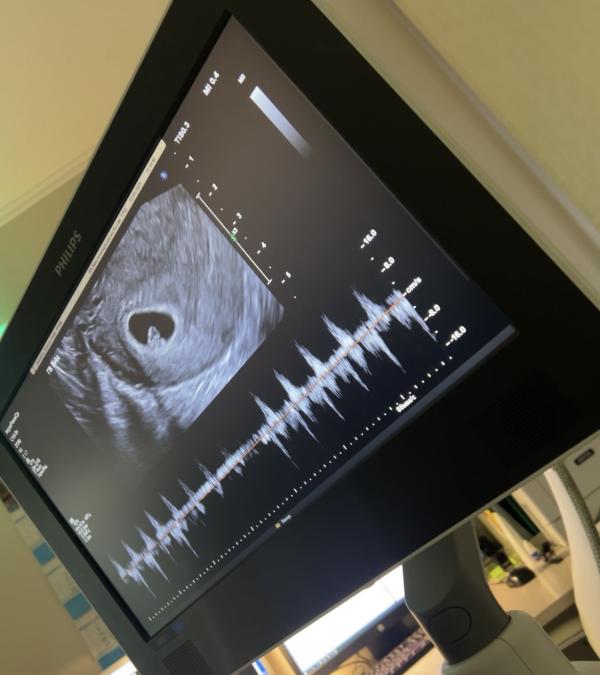

Вот оно, самое долгожданное и волшебное эхо! ❤️ Сегодня я услышала, как бьется сердечко моего малыша.

Но сегодня — абсолютное счастье и спокойствие. Это крошечное сердечко стучит со скоростью 118 ударов в минуту, и это самый лучший звук на свете. Он значит только одно: сейчас всё хорошо, и ради этого стоит всё преодолеть. 🥹